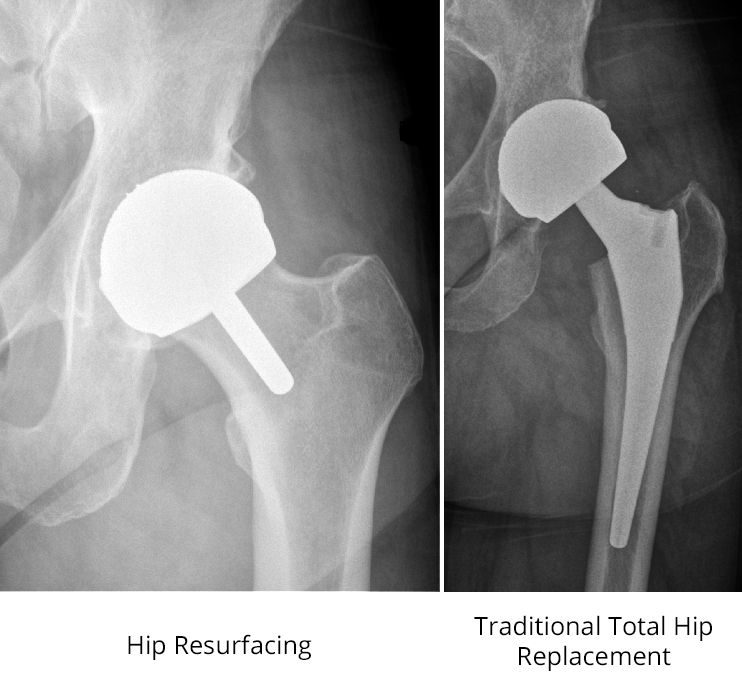

x-rays of hip resurfacing and total hip replacement

(Left) In this X-ray of a hip resurfacing taken from the front, a metal cap now covers the femoral head, and a small stem is seen in the femoral neck. A metal socket is also in place. Unlike the traditional total hip replacement shown on the right, the femoral head and neck are not removed.

In a traditional total hip replacement, the head of the thighbone (femoral head) and the damaged socket (acetabulum) are both removed and replaced with metal, plastic, or ceramic components.

In hip resurfacing, the femoral head is not removed but is instead trimmed and capped with a smooth metal covering. The damaged bone and cartilage within the socket are removed and replaced with a metal shell, just as in a traditional total hip replacement.